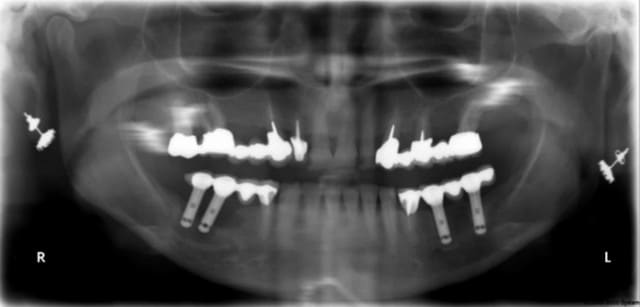

photos et radio de mauvaise qualité je n'avais pas mon matériel sous la main ce matin mais uniquement la caméra endobuccale que je ne manie que rarement (ca se voit),depuis un cambriolage je ne laisse plus rien de valeur facilement transportable .Mais j'ai pensé à ton sujet alors j'ai paré au plus pressé

Ce patient( proche de la famille) a été équipé site de 36 37 il y à deux ans et mis en provisoire à l'époque parti à 700 km du cabinet me contacte mardi en me disant qu'il revenait pour la toussaint mais qu'il avait un petit souci du coté droit....

et voilà le résultat : fracture des deux petites provisoires au niveau de l'extension mesiale ; voussure vestibulaire que l'on devine malgré la photo de mauvaise qualité .